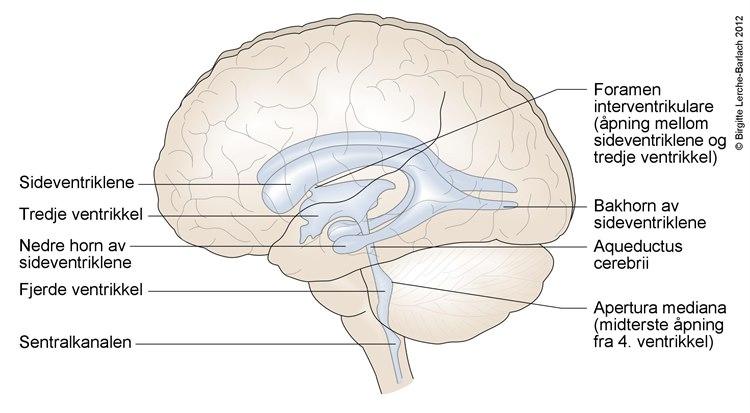

Inne i hjernen er det fire hulrom (ventrikler) som er forbundet med hverandre, og som er fylt med væske, cerebrospinalvæsken (se nedenfor). Ventriklene har åpen forbindelse med det lange, tynne hulrommet som går nedover i ryggkanalen og med hulrommet mellom det bløte hjernevevet og kraniet (se nedenfor). Alle disse hulrommene inneholder cerebrospinalvæske.